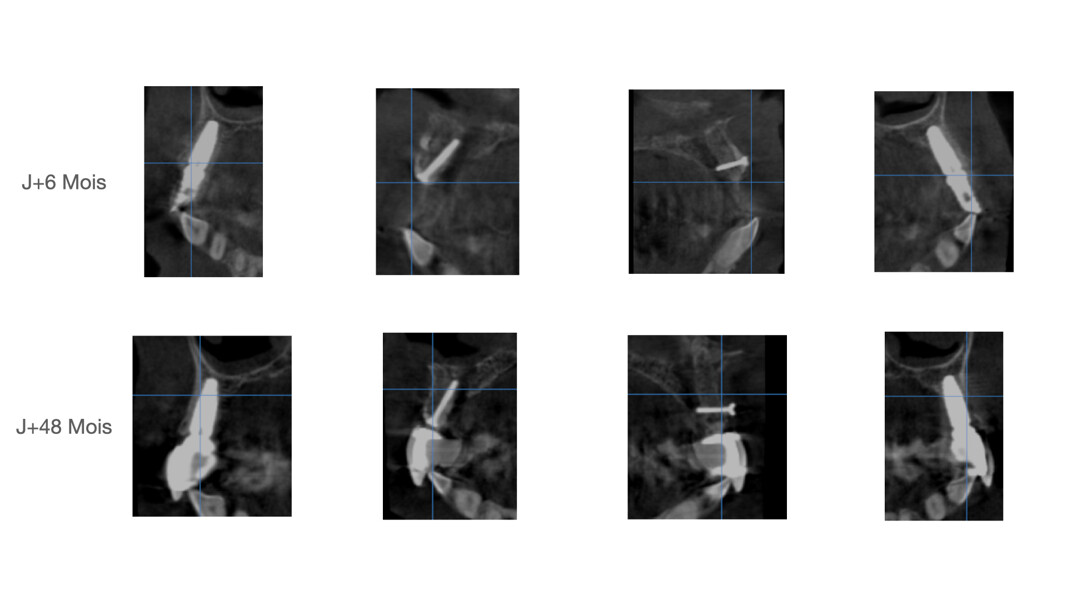

La patiente est suivie annuellement (cliniquement et radiologiquement), afin de contrôler l’évolution de l’ankylose des greffons radiculaires, leur résorption ainsi que le bon maintien du volume greffé (recul 48 mois postopératoire [Fig. 22]).

La patiente est suivie annuellement (cliniquement et radiologiquement), afin de contrôler l’évolution de l’ankylose des greffons radiculaires, leur résorption ainsi que le bon maintien du volume greffé (recul 48 mois postopératoire [Fig. 39]).